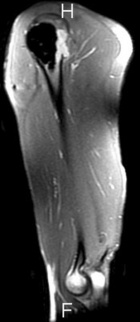

28 y/o male eight years s/p curettage and cementation for a right proximal humerus lesion found to be an aggressive enchondroma; presents with increasing R shoulder pain, worse with activity and direct pressure

PE: Healed surgical scar R shoulder, no TTP, mild edema, no LAN; FAROM, neurovascularly intact, 5/5; pain reproduced with shoulder extension and pulling